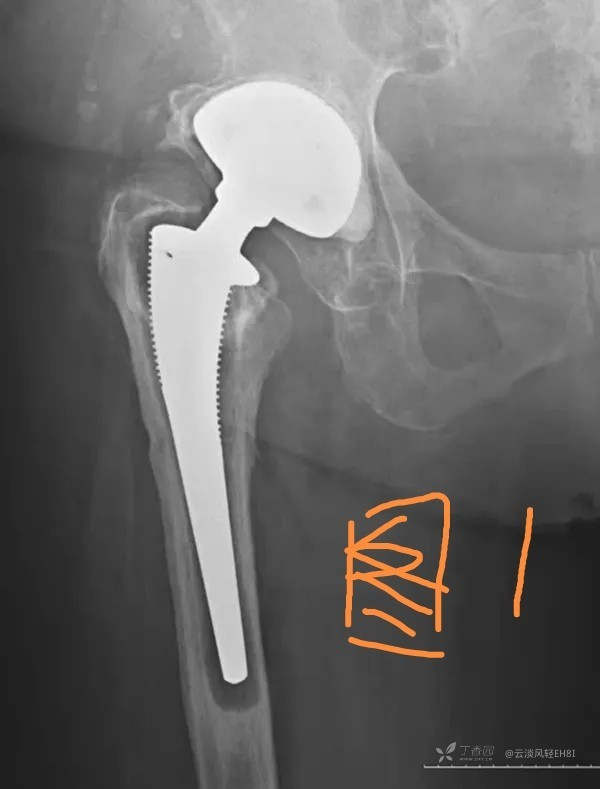

一、无菌性松动(图1-2)

大多数松动发生在假体柄和骨水泥之间间隙,偶然发生在髋臼帽与骨水泥之间。无菌性松动的诊断,应包括临床松动和X线松动。临床松动诊断主要根据大腿和髋部疼痛等症状。X线松动主要有以下征象:①假体周围透亮带超过2mm,且有持续增宽趋势。②假体移位下沉或旋转等超过4mm;③关节造影同时行牵引见造影剂向假体与骨界面渗入,仅据其中一项即可诊断。